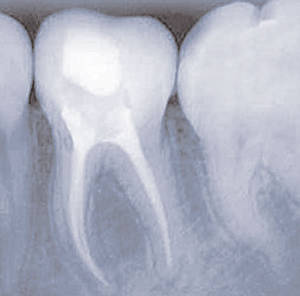

Früher musste ein Zahn, der bis in die Wurzel erkrankt war, oftmals entfernt werden. Unser modernes Konzept zur Endodontie (Wurzelkanalbehandlung) ermöglicht es heute, diese Zähne zu erhalten.

Als Therapie bleibt in beiden Fällen nur die Wurzelkanalbehandlung. Primäres Ziel dieser Behandlung ist es, die komplexen Wurzelkanäle von Geweberesten, Bakterien und Giftstoffen restlos zu reinigen. Dafür eignen sich hand- wie auch computergesteuerte flexible Nickel-Titaninstrumente und chemische Spülungen. Neben diesem Instrumentarium erfordert die Behandlung vor allem einen hohen Zeitaufwand. Sind mehrere Sitzungen zur Desinfektion der Kanäle  nötig, wird der Zahn zwischen den einzelnen Terminen mit einer medikamentösen Einlage versehen. Ist der Zahn wieder entzündungsfrei, werden abschließend die Kanäle mit einem speziellen Füllungsmaterial verschlossen.